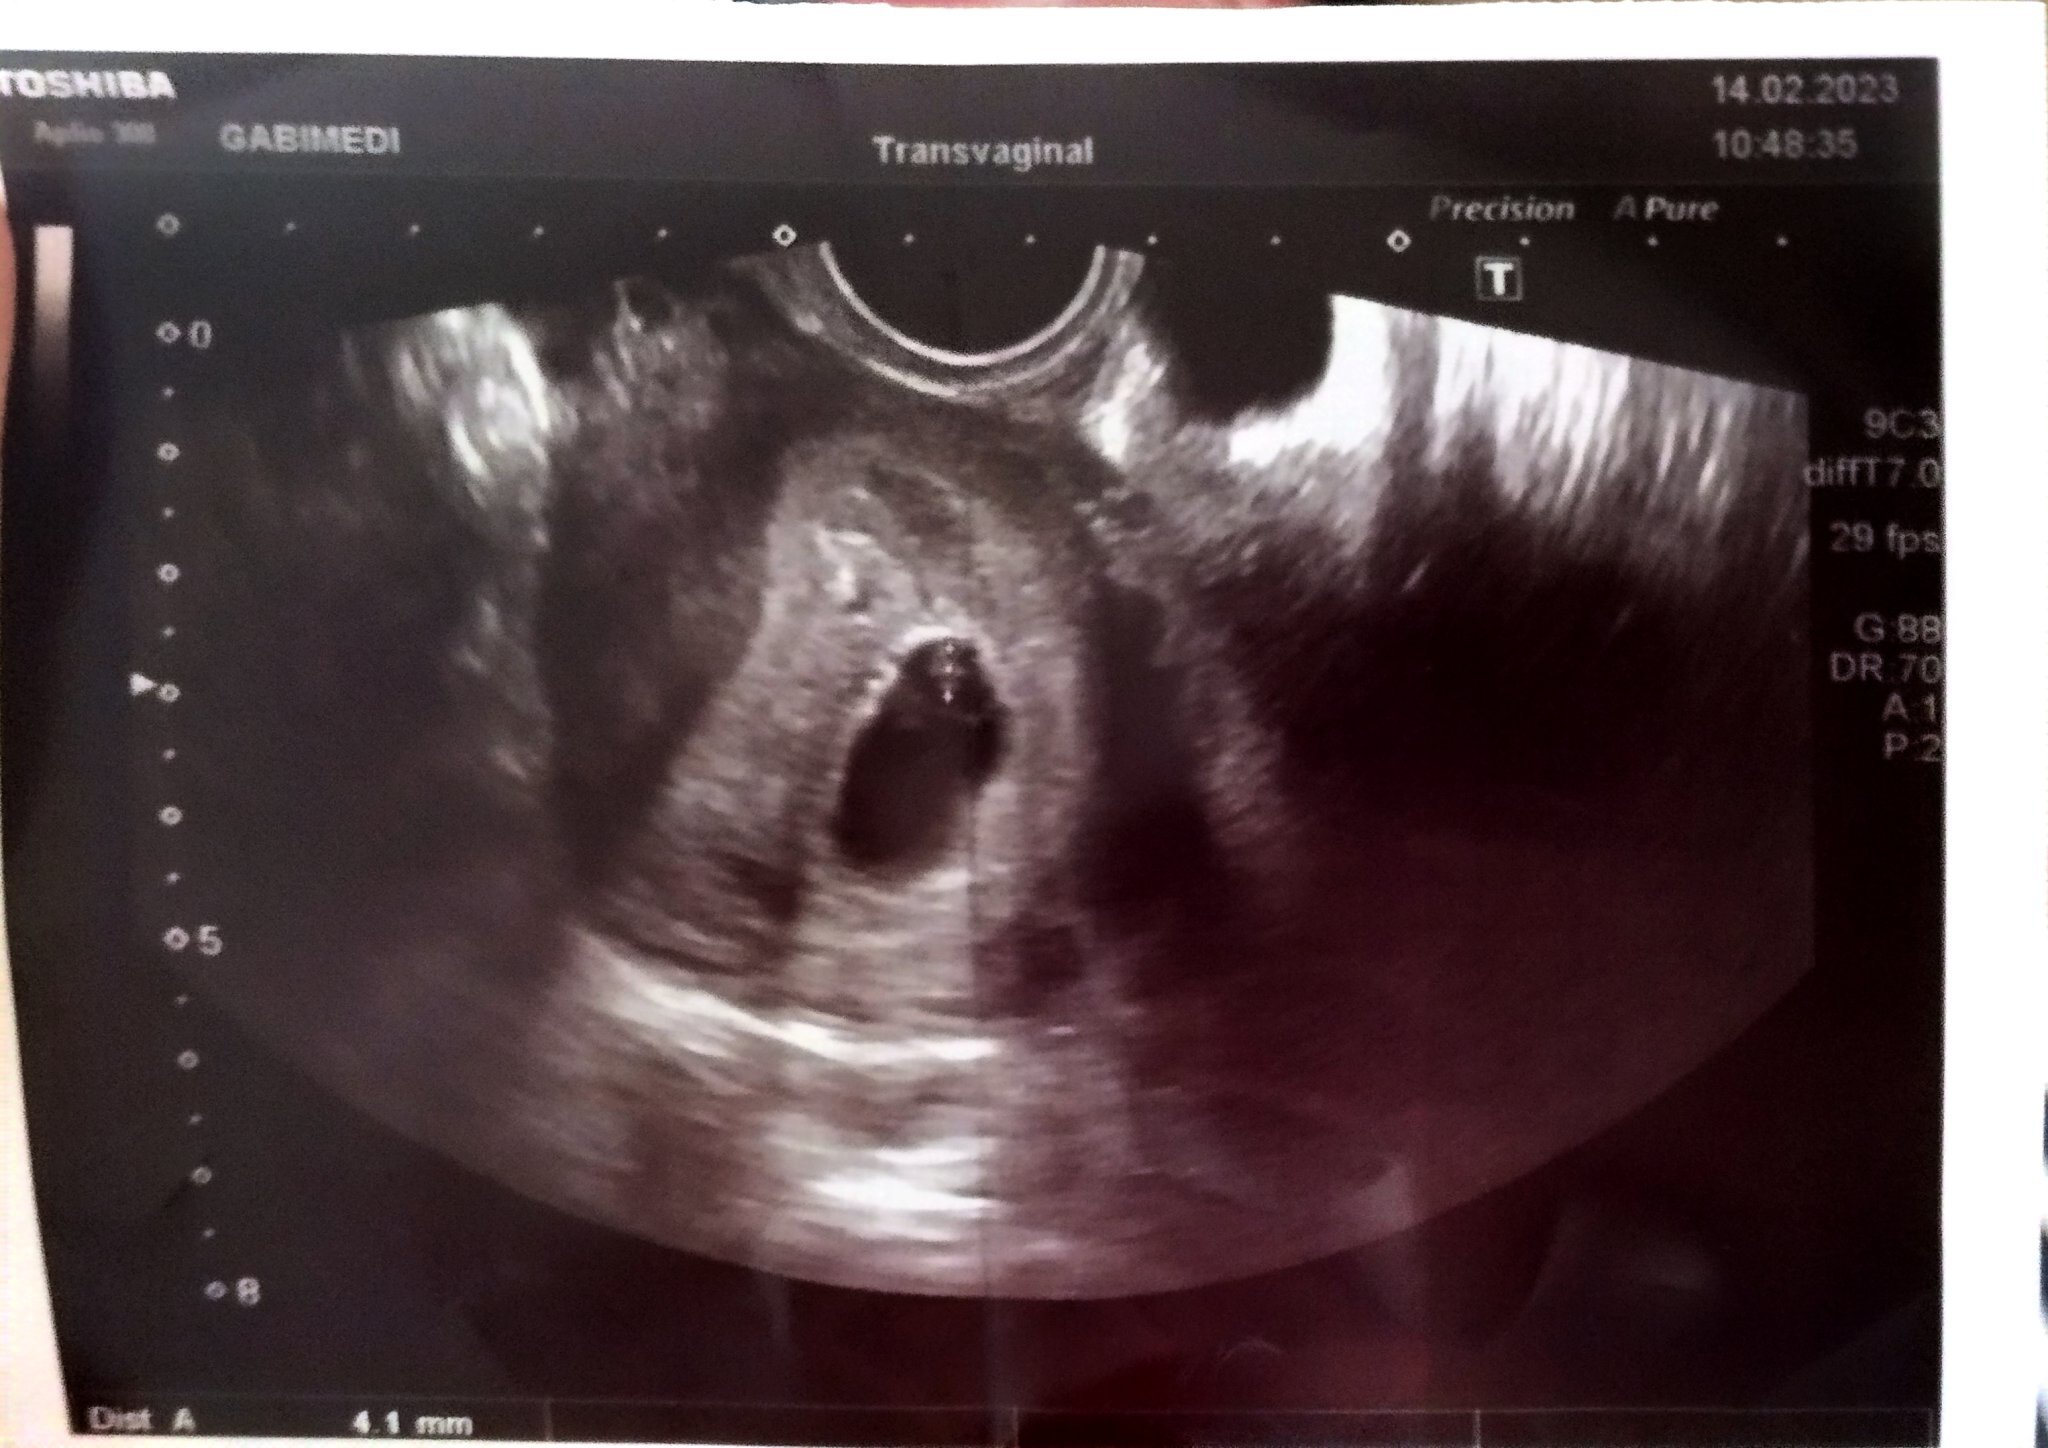

Нормално ли е при 4+6 седмици бременност да се види само сакче без жълтъчно мехурче?